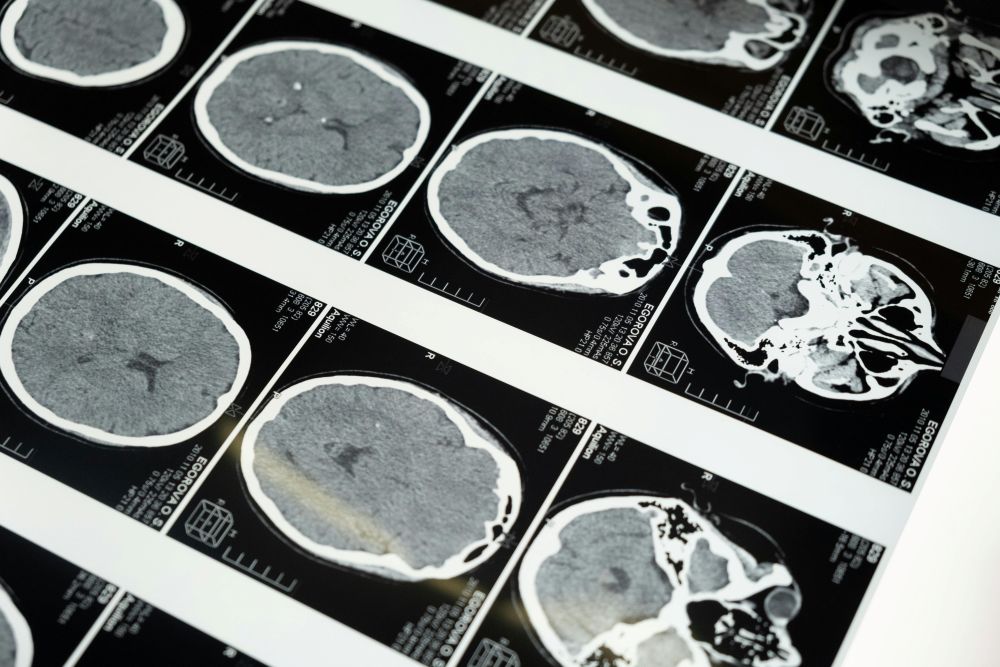

Znanstvenici su analizirali oko 3800 skupova podataka od ljudi u dobi do 90 godina starosti bez poznatih neuroloških bolesti. Koristili su difuzijske MRI snimke koje prikazuju neuronske veze prateći kretanje molekula vode kroz moždano tkivo. "Pomoću toga identificirali smo četiri važne topološke prekretnice tijekom života - u dobi od oko 9, 32, 66 i 83 godine", rekli su znanstvenici.

FOTO: Pexels (Ilustracija)